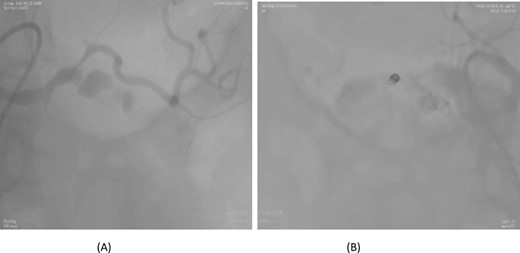

A 56-year-old female underwent a pancreaticoduodenectomy (PD) for pancreatic head adenocarcinoma. On the 6th postoperative day, she presented with nausea and vomiting. A contrast-enhanced CT scan revealed the presence of a pseudoaneurysm originating from the common hepatic artery. Angioembolization was promptly performed to control the bleeding. The procedure was successful, and the patient recovered well postoperatively. At follow-up, the patient was doing fine with no further complications (Fig. 2).

Case 2. (A) CT angiogram showing pseudoaneurysm CHA. (B) Angioembolization of CHA with gel foam